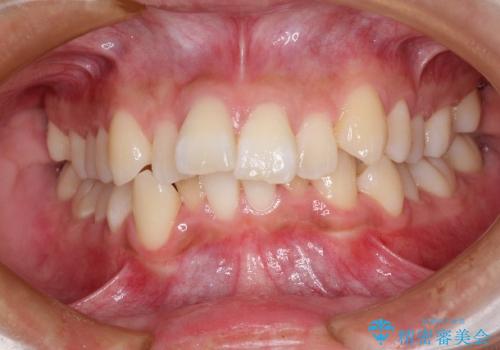

前歯の乱れをスッキリ解消!抜歯矯正で整えた美しい歯並び

担当医 河口智英